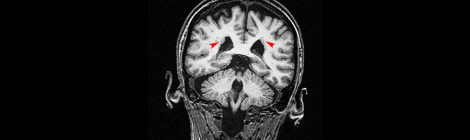

Heterotopias in the Brain: When Neurons Get a Little Lost

I’ve talked a little about heterotopias in the past although I haven’t focused on them considerably. But that’s about to change today because they are fascinating occurrences which happen occasionally […]